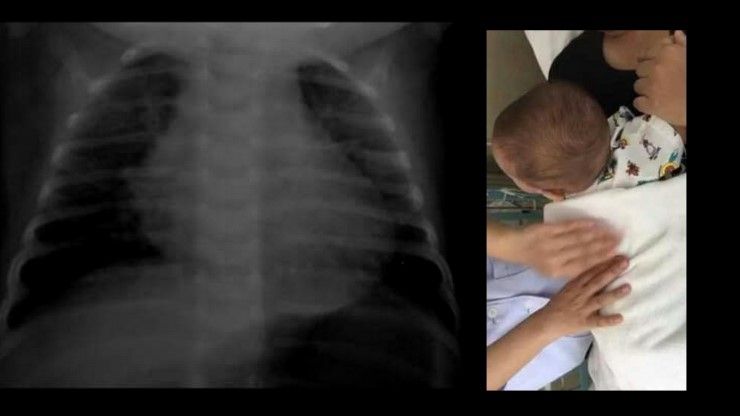

เมื่อวันที่ 21 พ.ย. สังคมออนไลน์ให้ความสนใจเรื่องราวที่ถูกเผยเเพร่โดยเฟซบุ๊กชื่อ พิม จ๋า ซึ่งได้โพสต์เอาไว้ในกลุ่ม HerKid รวมพลคนเห่อลูก โดยมีภาพเอ็กซเรย์ปอดของเด็กเล็ก พร้อมกับภาพที่ต้องพ่นยา ซึ่งคุณแม่รายนี้ระบุว่า ลูกเกิดอาการปอดติดเชื้อเป็นหอบ สาเหตุมาจากการได้รับควันบุหรี่มากเกินไป

"เตือนนะคะ (แชร์ได้) คุณพ่อคุณแม่ที่ชอบสูบบุหรี่ในห้อง เคสนี้เกิดขึ้นกับลูกเราเองค่ะ ตอนแรกแม่ก็นึกว่าลูกไข้แบบธรรมดาเพราะกลับมาจากฉีดวัคซีนแต่น้องไอมากไอจนอ้วกแล้วหายใจลำบากน้องร้องทั้งคืนฟังเสียงน้องหายใจจะได้ยินเหมือนเสียงนกหวีดเลยรีบพาน้องไปโรงพยาบาล ผลออกมาปรากฎลูกเปนหอบและปอดติดเชื้อค่ะ และตอนนี้ปอดน้องก็หายไปครึ่งนึง 1 ข้างคะ #คุณหมอบอกว่าสาเหตุเป็นเพราะได้สูดรับควันบุหรี่มากไป ต้องคอยพ่นยาทุก 2 ชั่วโมงเลยค่ะ

ที่น้องได้รับควันบุหรี่มากๆเพราะว่าแฟนชอบดูดบุหรี่ไม่ดูดในบ้านก็จริง แต่ควันที่ติดมาจากเสื้อที่แฟนดูดบุหรี่แล้วมาอุ้มลูกแล้วลูกเอาหน้าซบกับเสื้อผ้าแฟน ที่บ้านเลี้ยงไก่ด้วย มันจะมีตัวไรซึ่งเรามองไม่เห็นเป็นสาเหตุด้วย &<28557;&<28557;สงสารลูกเลย หมอต้องคอยเคาะเสลด ไม่มีไครเจตนาให้มันเกิดขึ้นทั้งสิ้น ตอนนี้หมอพ่นยาทุก2ชม. และดูดน้ำมูก เคาะปอดทุก 4 ชั่วโมง" หญิงสาวเล่า"